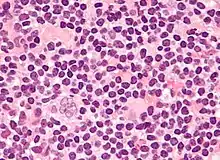

| Nodular sclerosing HL | Is the most common subtype and is composed of large tumor nodules showing scattered lacunar classic RS cells set in a background of reactive lymphocytes, eosinophils and plasma cells with varying degrees of collagen fibrosis/sclerosis. | C81.1 | M9663/3 |

| Mixed-cellularity subtype | Is a common subtype and is composed of numerous classic RS cells admixed with numerous inflammatory cells including lymphocytes, histiocytes, eosinophils, and plasma cells without sclerosis. This type is most often associated with Epstein-Barr virus infection and may be confused with the early, so-called 'cellular' phase of the nodular sclerosing subtype. This type of Hodgkin lymphoma is most commonly seen in immunocompromised people. | C81.2 | M9652/3. |

_mixed_cellulary_type.jpg.webp)

Microscopic examination of the lymph node biopsy reveals complete or partial effacement of the lymph node architecture by scattered large malignant cells known as Reed-Sternberg cells (RSC) (typical and variants) admixed within a reactive cell infiltrate composed of variable proportions of lymphocytes, histiocytes, eosinophils, and plasma cells. The Reed–Sternberg cells are identified as large often bi-nucleated cells with prominent nucleoli and an unusual CD45−, CD30+, CD15+/− immunophenotype. In approximately 50% of cases, the Reed–Sternberg cells are infected by the Epstein–Barr virus.[39]